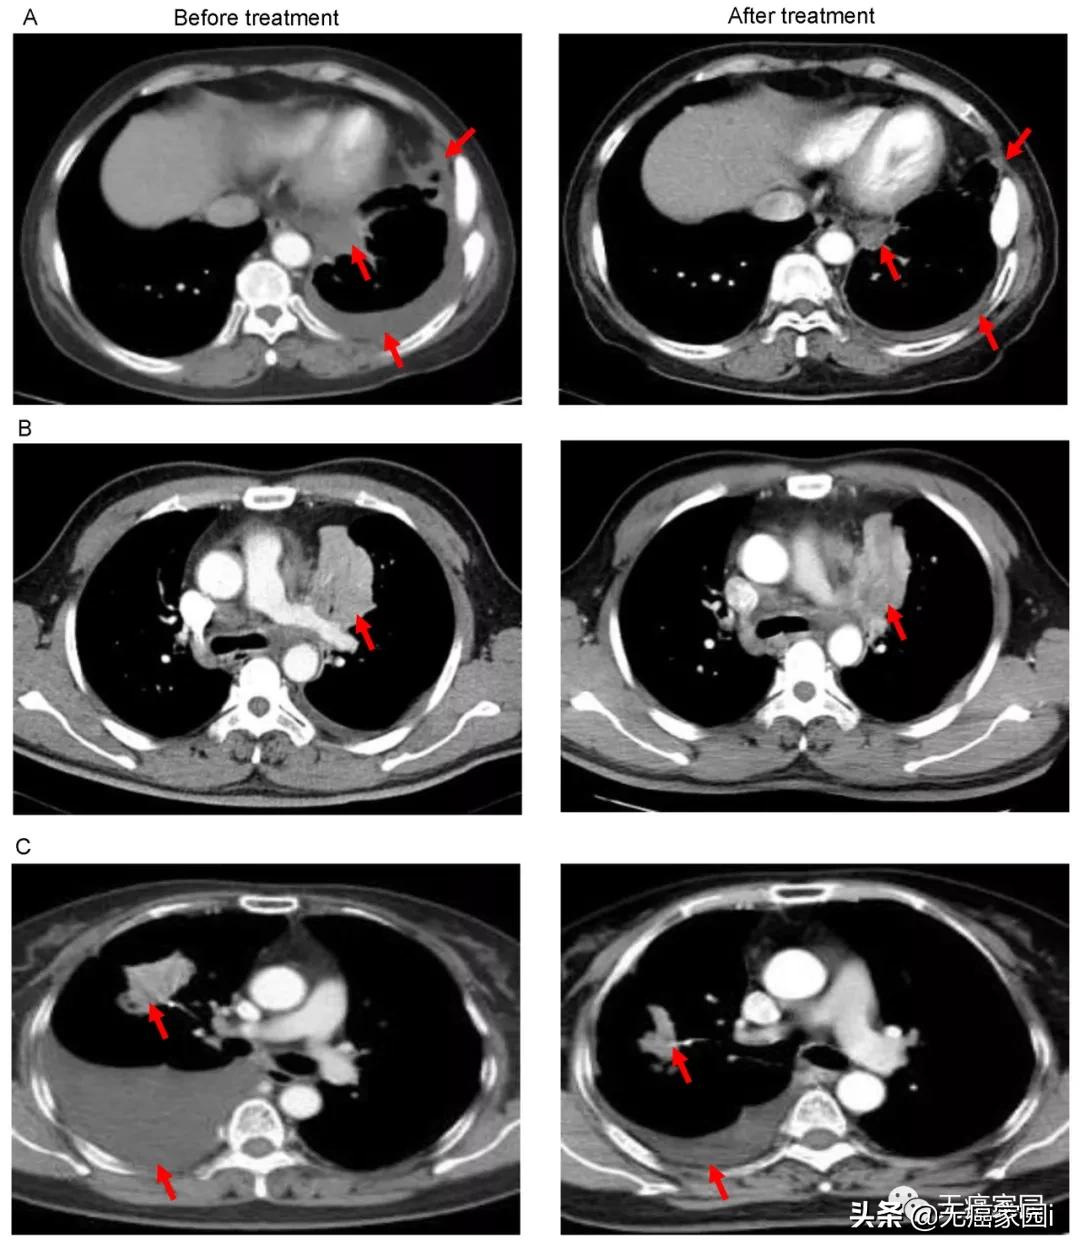

图A中患者1在输注CAR-T细胞后,通过CT扫描显示其胸腔积液减少,转移性肺门淋巴结和胸膜结节轻度缩小(箭头)。

图B中CT图像显示患者8的原发性肿瘤缩小(箭头);

图C中CT检查发现CAR-T治疗后患者9的胸腔积液吸收和肺部病变明显消退。